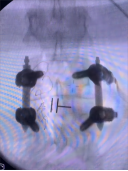

5.微创胸腰椎固定融合技术

微创胸腰椎固定融合技术适用于治疗腰椎间盘突出症、腰椎管狭窄症、腰椎失稳、腰椎滑脱、胸腰椎骨折、腰椎峡部不连及部分翻修手术等。其与传统TLIF技术相比,该技术通过最小的创伤即能达到和开放腰椎减压融合手术同样的临床效果,同时可减少并发症,实现病人快速康复的目的。